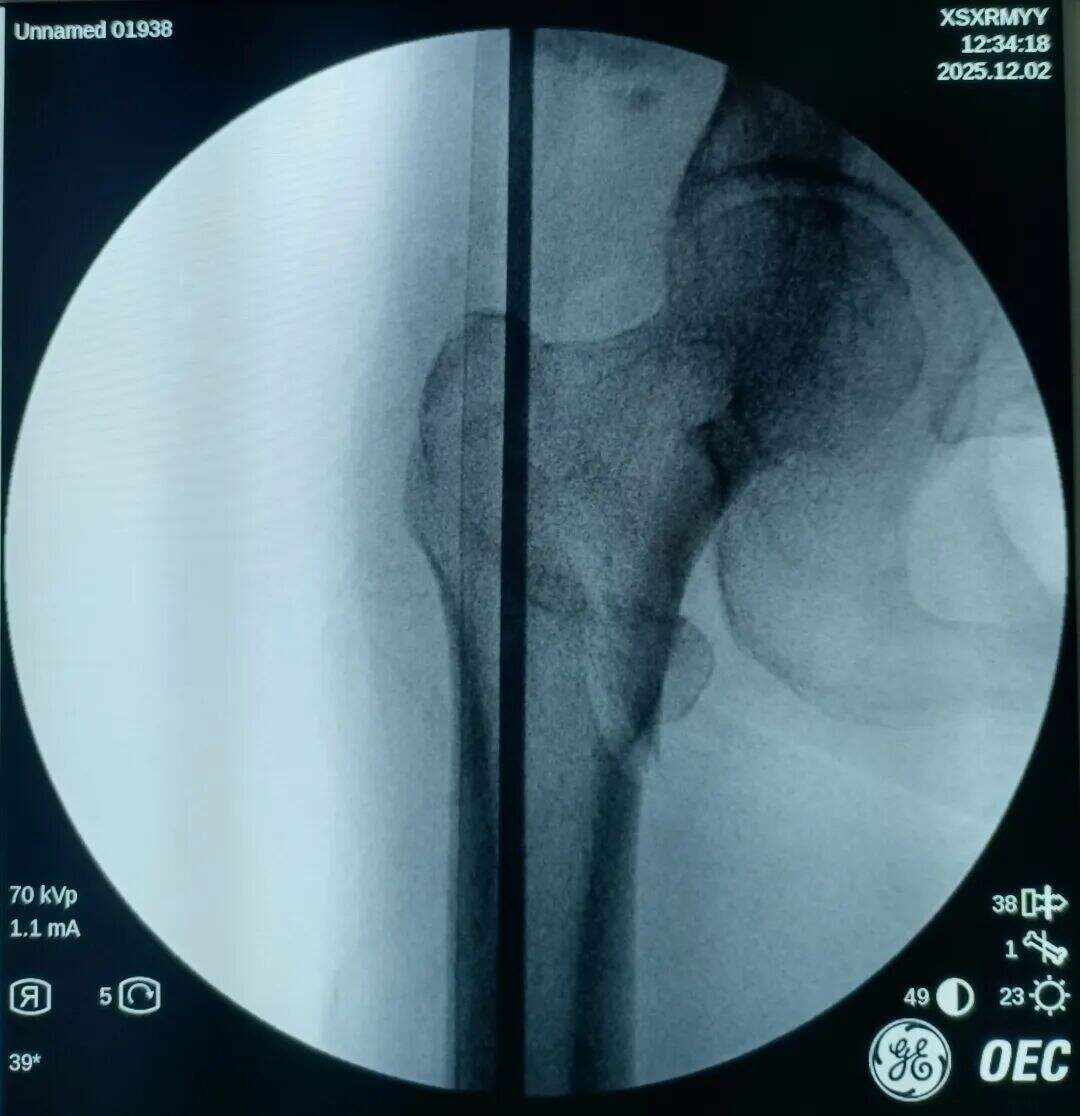

Poskus zaprta zmanjšanja, vendar ni uspel. Več vlečne sile je uporabljeno, več je bilo premaknjen v višji del zaradi vlečenja iliopsoas mišice.

Narezen je bil 2 cm prednji mini-rez. Mesto zloma je bilo opazovano z prstom. Ugotovljeno je bilo, da je proksimalni fragment premaknjen navzgor, distalni fragment pa nazaj in zaklenjen. V mesto zloma je bil vstavljen klešča; pod vodstvom prsta v kombinaciji s kleščo so bili zaklenjeni fragmenti odklenjeni. Nato je bila klešča uporabljena za ohranitev kakovosti redukcije z medialno in lateralno kompresijo. Izvedena je bila običajna lokalizacija, vstavitev vodilne žice ter standardni kirurški postopek.

Medularni kanal je bil ozek. Nobenega razširjanja ni bilo izvedeno. Intramedularni klin s premerom 9 mm je bil vstavljen v tesen fit. Prilagoditev anteversije cefalomedularnega vijaka se je izkazala za težko.